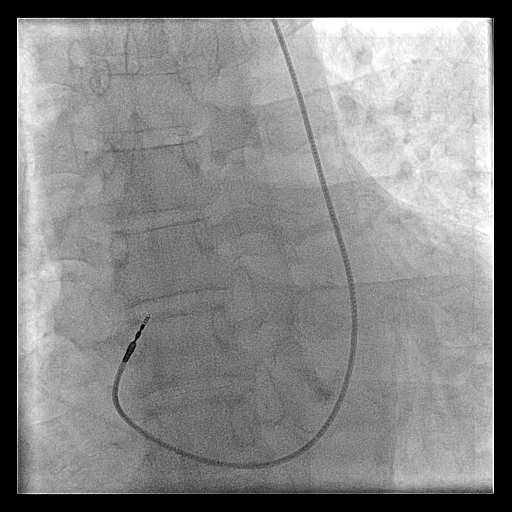

Post implant

Post implant care

Post procedure care

• Immobilisation / bed rest ?

• Analgesia

• Chest X ray after 4-6 hours

• ECG / Pacemaker check

• Antibiotics ?

• Shower ?

Post procedure CXR

pneumothorax_post_ppm.jpg